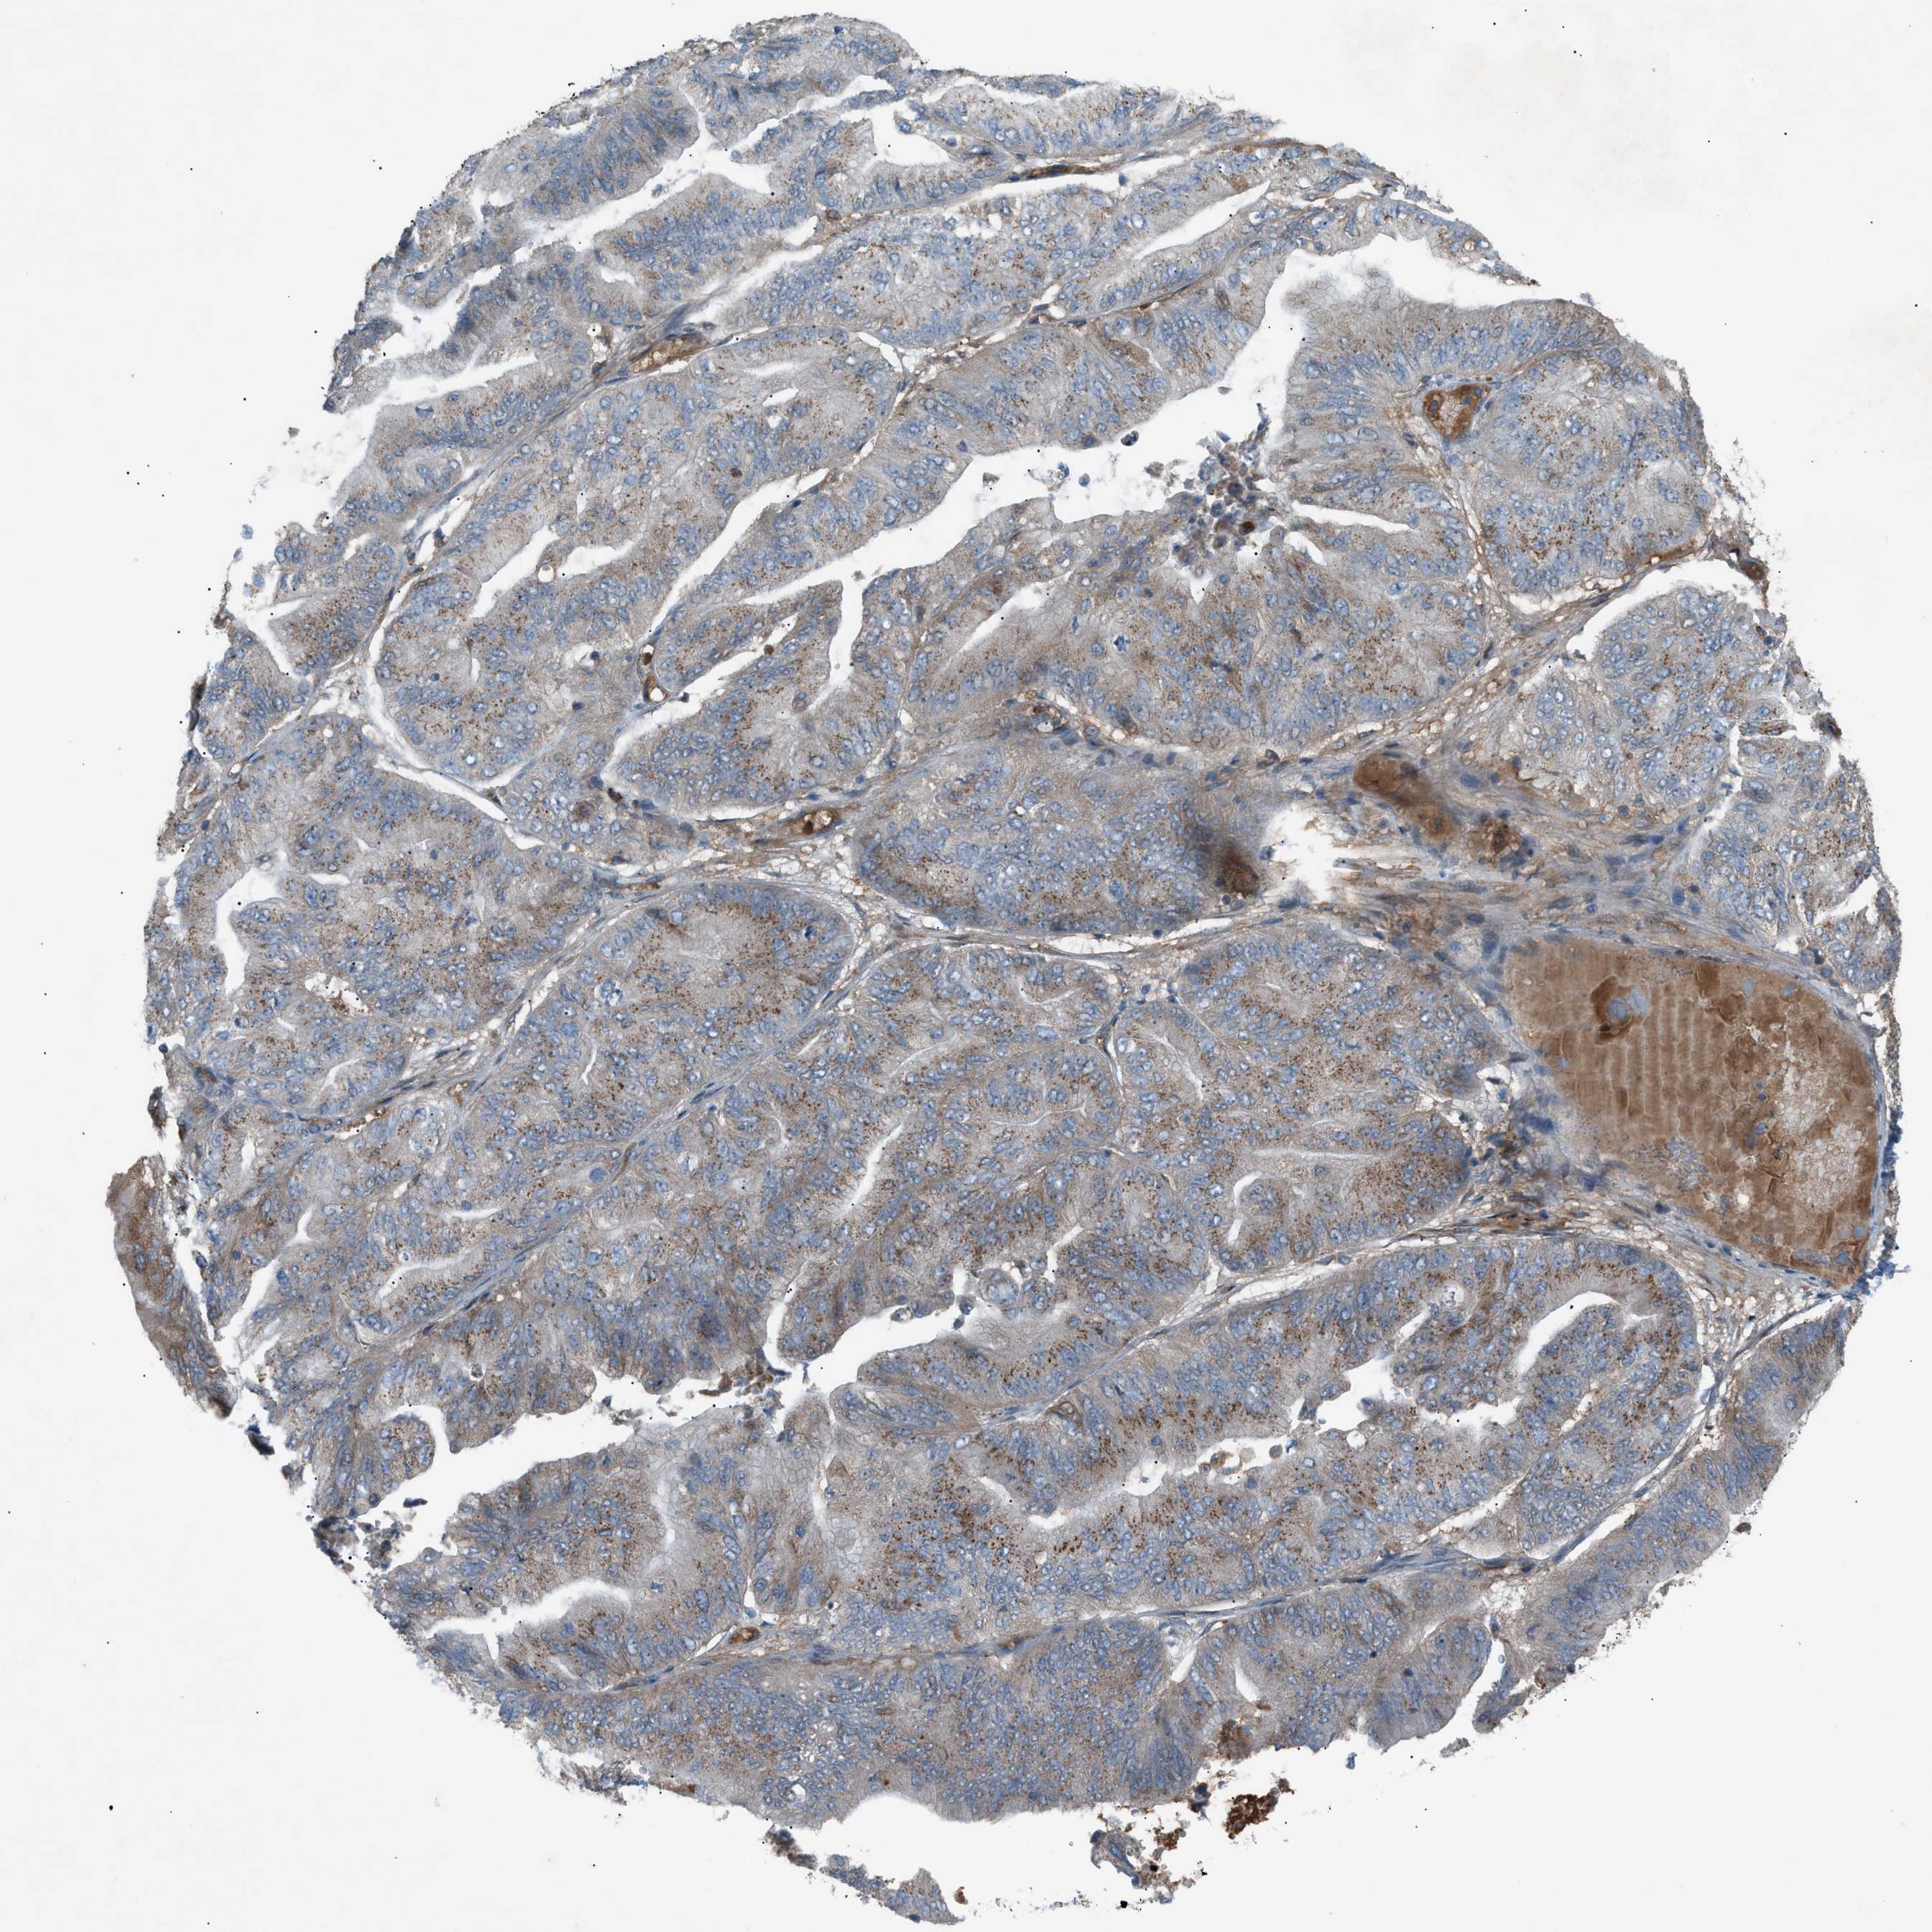

OVARIAN CANCER - Protein expressioni

A mouse-over function shows sample information and annotation data. Click on an image to view it in a full screen mode. Samples can be filtered based on level of antibody staining by selecting one or several of the following categories: high, medium, low and not detected. The assay and annotation is described here.

Note that samples used for immunohistochemistry by the Human Protein Atlas do not correspond to samples in the TCGA dataset.

Antibody stainingi

Antibody staining in the annotated cell types in the current human tissue is reported as not detected, low, medium, or high, based on conventional immunohistochemistry profiling in selected tissues. This score is based on the combination of the staining intensity and fraction of stained cells.

Each image is clickable and will lead to virtual microscopy that enables deeper exploration of all samples and also displays staining intensity scores, fraction scores and subcellular localization as well as patient and tissue information for each sample.

Antibody HPA015323

Antibody HPA015810

Carcinoma, endometroid

Cystadenocarcinoma, serous, NOS

Cystadenocarcinoma, mucinous, NOS

Carcinoma, NOS